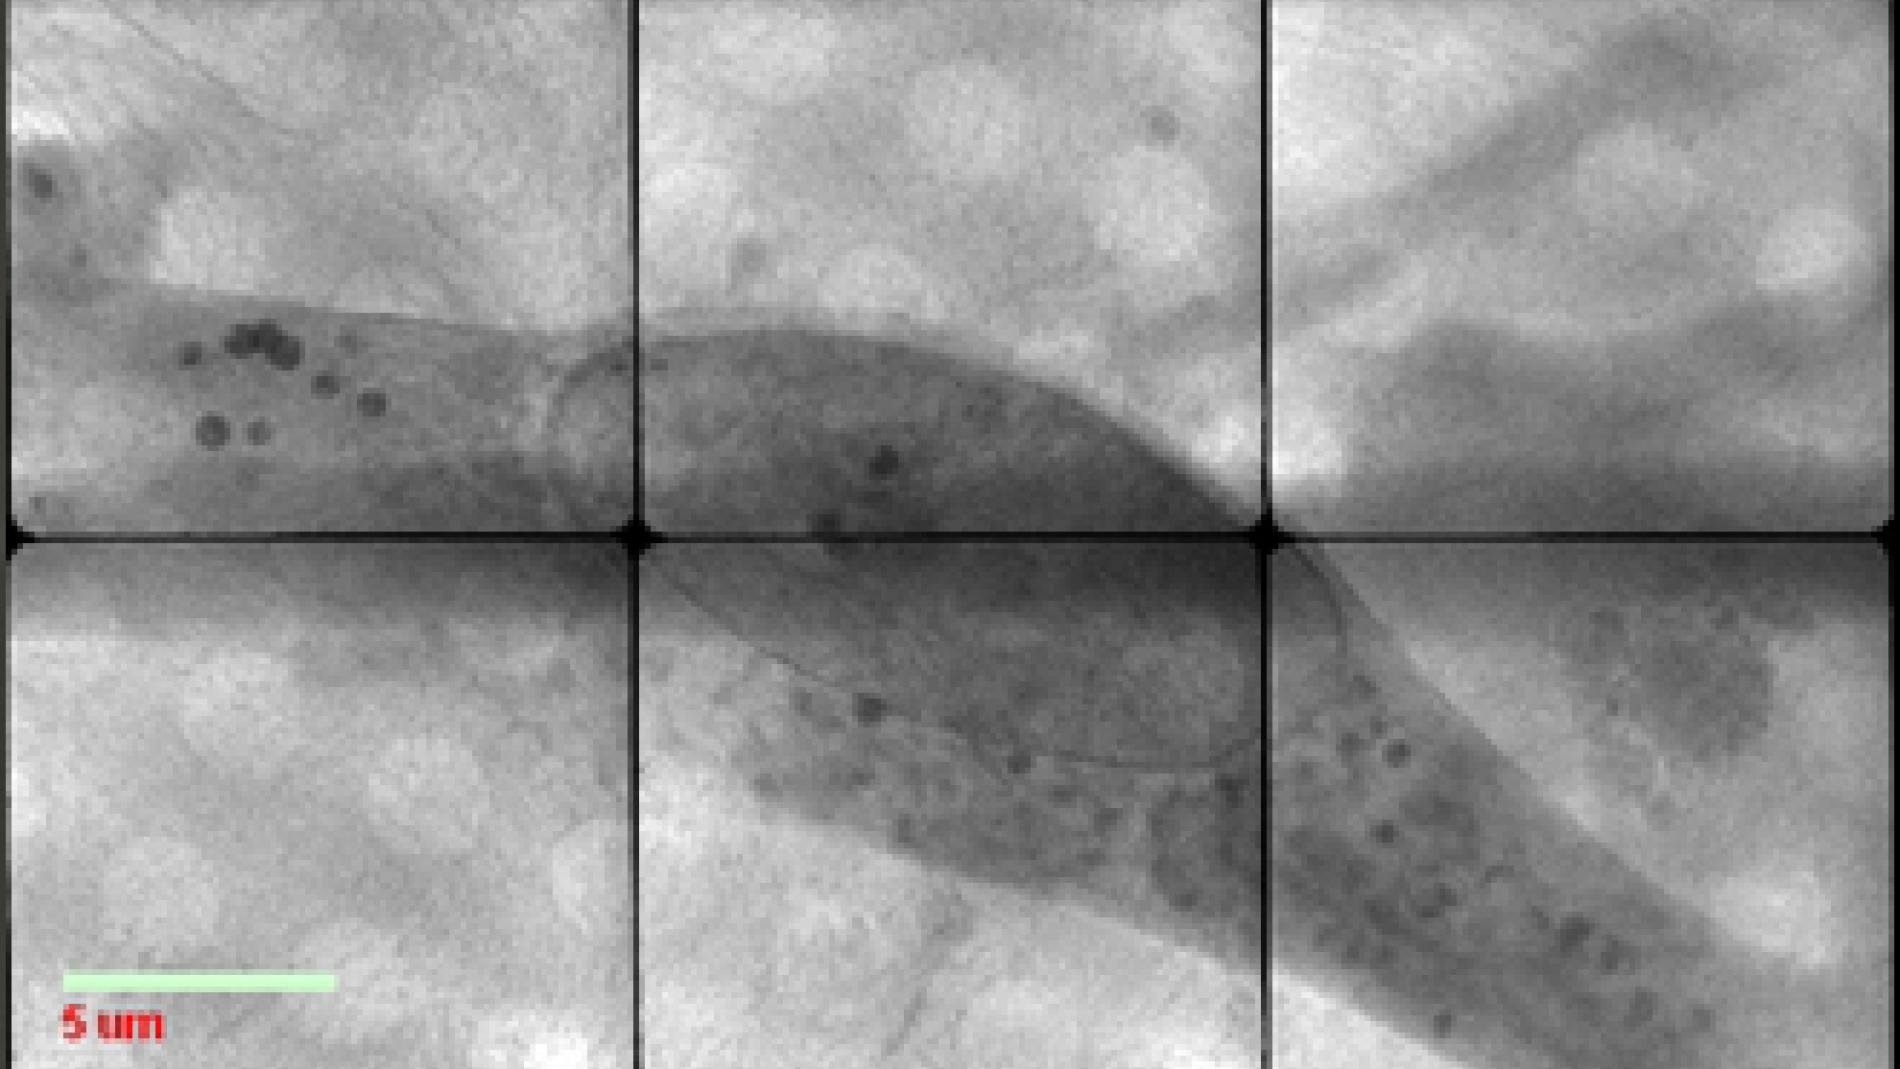

Researchers have guided endothelial progenitor cells to zones of the brain by applying a magnetic field

A study from Vall d’Hebron Institute of Research (VHIR), led by Dr. Anna Rosell, from the Neurovascular Diseases group, and Dr. Anna Roig, from the Nanoparticles and Nanocomposites group at the Institute of Materials Science of Barcelona (ICMAB-CSIC), has demonstrated that it is possible to guide the arrival of endothelial progenitor cells (EPCs) labeled with iron oxides in specific areas of the brain by applying externally a magnetic field. The research opens the door to non-invasive therapies to recover the neurological functions affected after suffering stroke. This technology, which has a patent pending with a majority participation of VHIR, together with ICMAB-CSIC, has been one of the five finalists of the "http://www.universal-biotech.com/index.php/lang-en/prixdelinnovation/finalists" Innovation Prize, a prestigious international contest organized by Universal Biotech with the aim to recognize the results of excellence in research and innovation in the biomedical sector. The prize is 100,000 euros. The results of the study, published in "http://www.nanomedjournal.com/article/S1549-9634(13)00273-6/abstract" Nanomedicine NBM, will be presented next September 12 in Paris, in front of an expert tribunal. At this moment, VHIR is seeking for a company interested in licensing this technology. Advancing through tissue regenerationThe Neurovascular Research Laboratory at VHIR is currently investigating new strategies based on vascular remodeling and enhancement of angio-vasculogenesis by endothelial progenitor cells. From a therapeutic point of view these cells could promote the formation of new vessels from the peri-lesional areas not affected after stroke and participate in tissue regeneration. But for a successful treatment is crucial to secure the arrival and graft of a sufficient number of transplanted cells into the brain areas of interest.With this study, the team of VHIR and ICMAB-CSIC has demonstrated that it would be possible to safely guide the arrival of these cells in specific areas of the brain where their graft could strengthen neurorepair mechanisms based on angio-vasculogenic responses. The experimental study also shows for the first time as EPCS labeled with iron oxide nanoparticles enhance their angiogenic function by increasing the ability to migrate and the secretion of trophic factors such as VEGF or FGF, all related to moderate oxidative stress levels within cells. According Dr. Rosell, this discovery "is a step forward for the research of new therapeutic strategies to enhance tissue regeneration not only from the graft of more functional stem/progenitor cells but also to from the delivery of trophic factors that could stimulate other processes such as neurogenesis". VHIR’s researcher is currently investigating the effects on the brain and tissue regeneration of such advanced cell therapies in experimental models of cerebral ischemia. Nonetheless, she insists that "the results suggest the potential of new and non-invasive therapies to regenerate the brain and recover the neurological functions affected by this devastating disease".